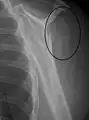

Proximal humerus fracture

A transverse fracture of the humerus shaft